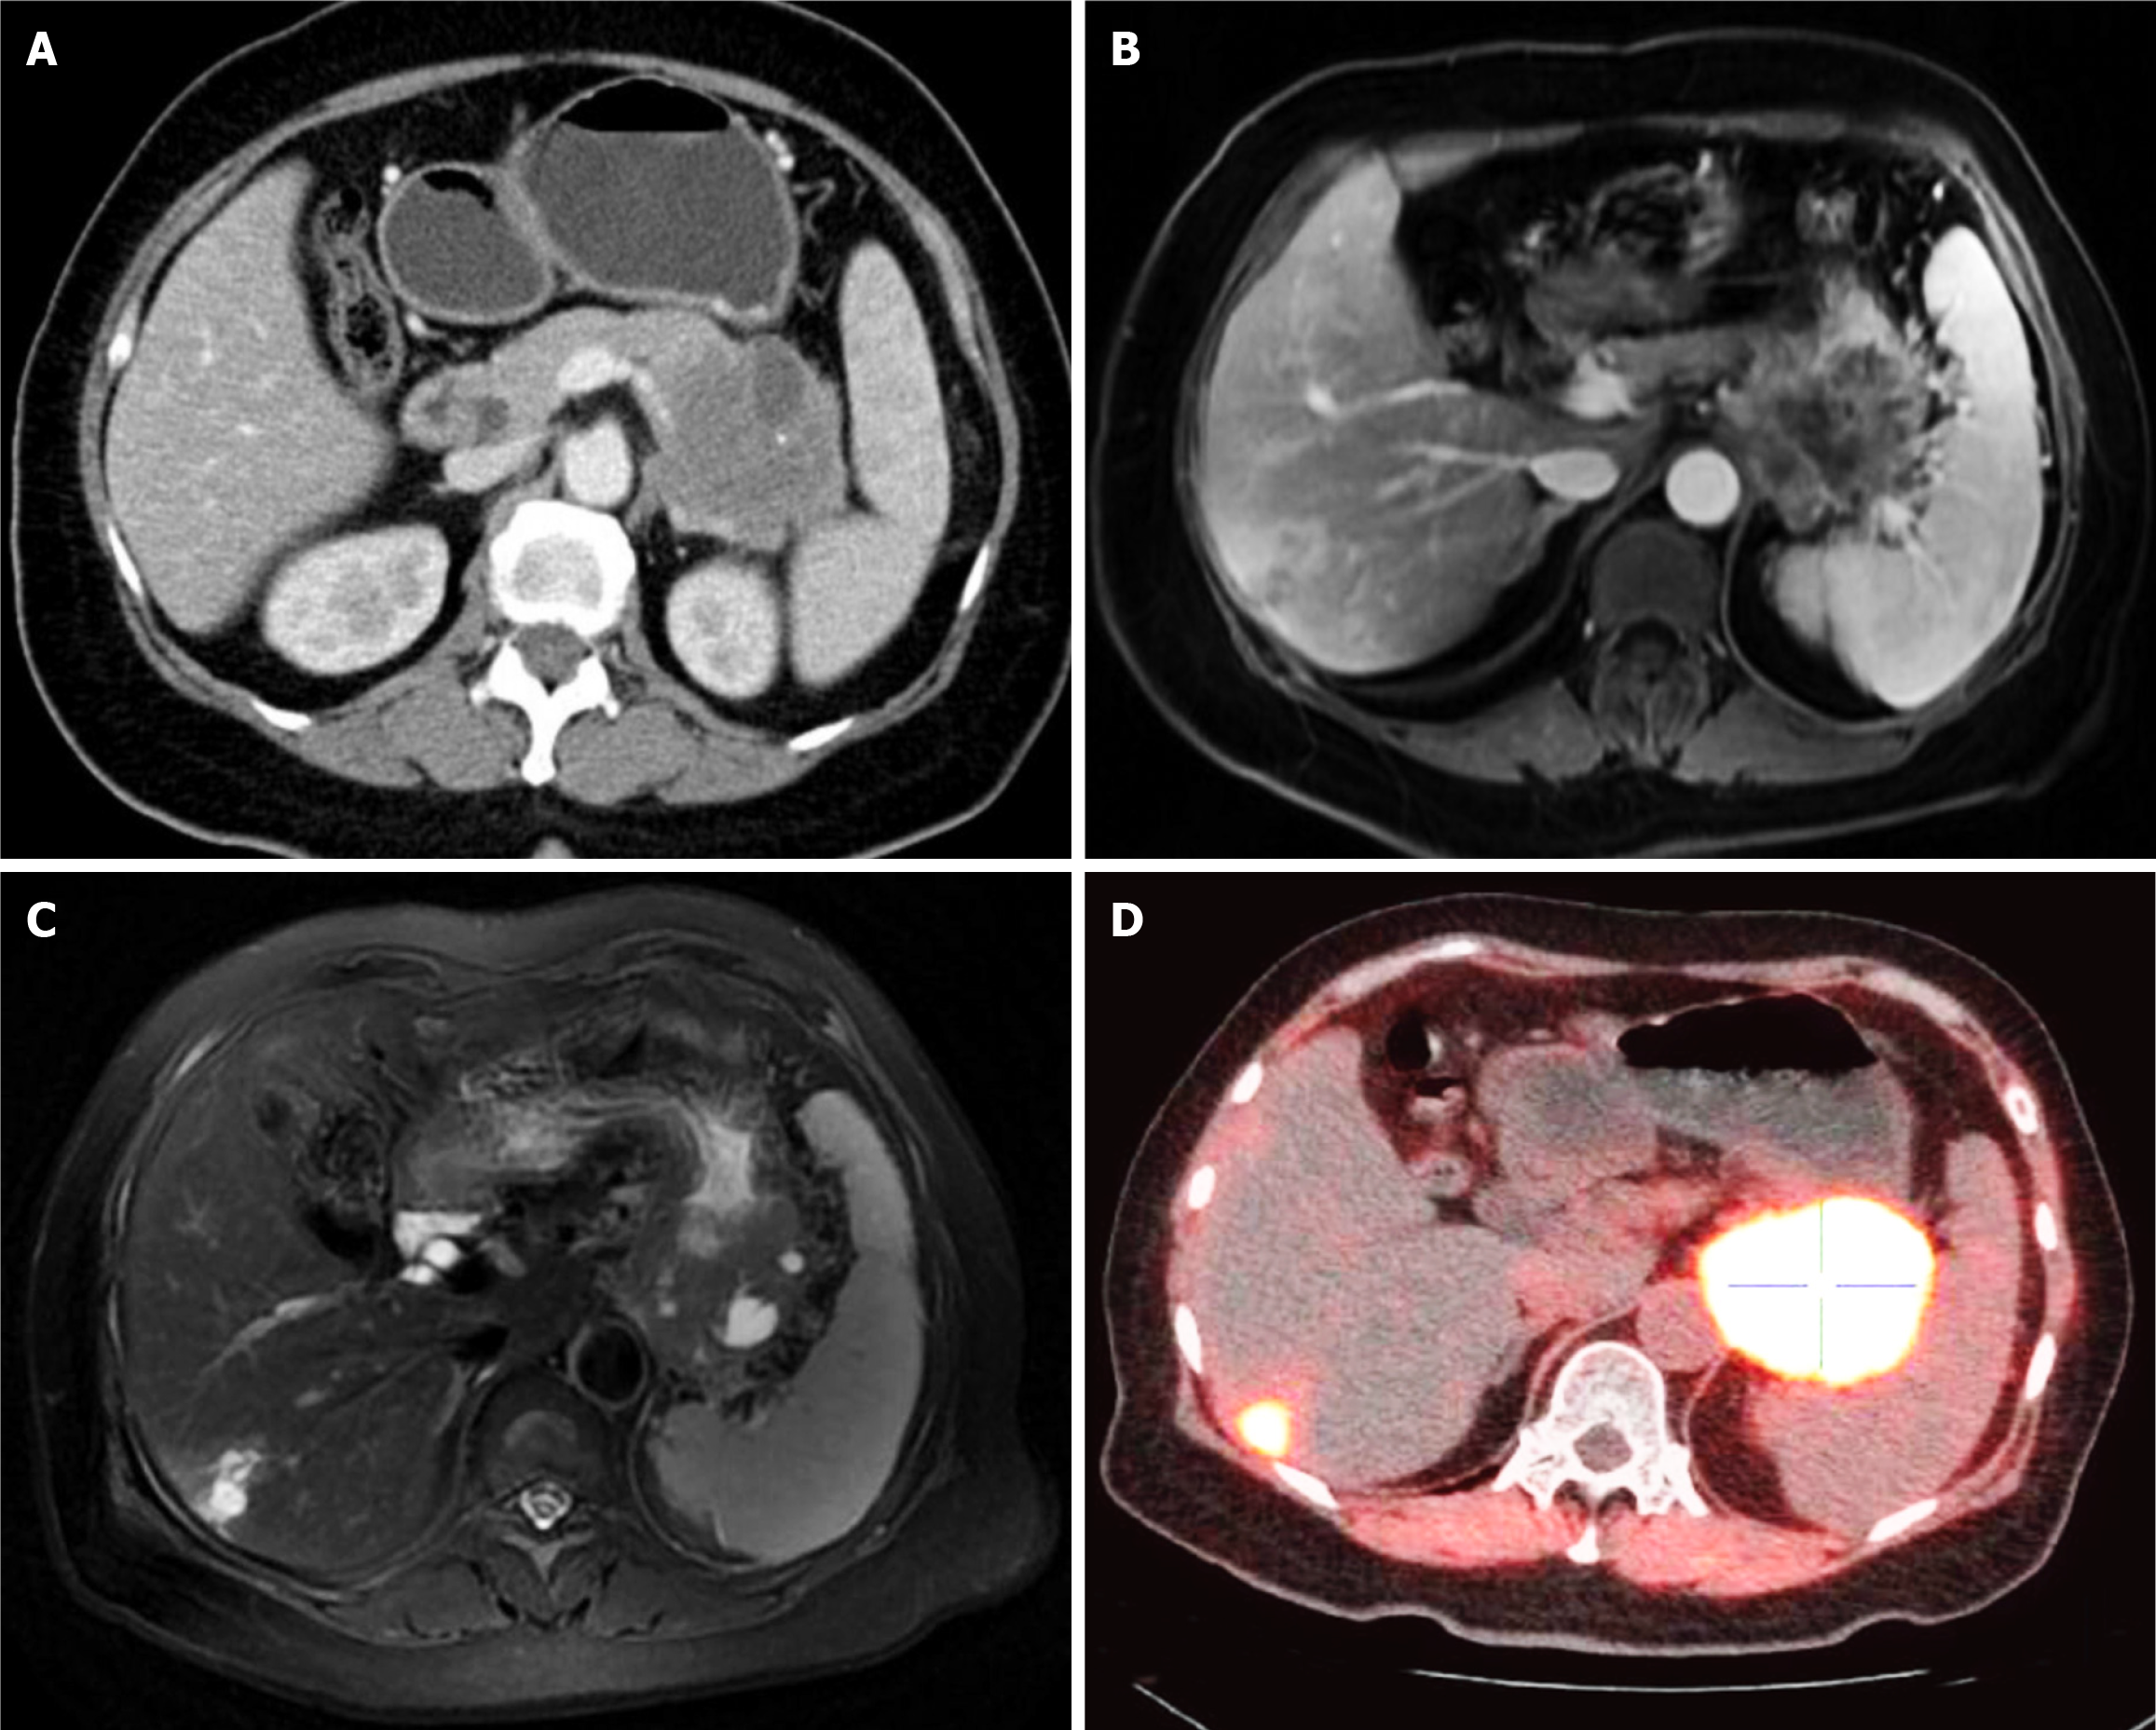

Figure 3 Imaging and nuclear medicine scans showed the advanced cystic mass on second admission to our hospital.

A: Contrast-enhanced computed tomography scan; B and C: Magnetic resonance imaging; D: Fluorine 18 fluorodeoxyglucose- and fluorine 18-labeled fibroblast-activation protein inhibitor-positron emission tomography/computed tomography.